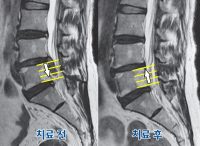

자생척추관절연구소 “디스크 심할수록 흡수 잘 돼” SCI(E)급 국제학술지 ‘근거중심 보완대체의학’ 최근호에 게재 (사진설명:코모리 구분법 상 class3에 해당하는 디스크 환자가 한의치료 후 class1으로 호전됐다.) [한의신문=윤영혜 기자]한의치료를 받은 디스크환자 10명 중 9명은 4년 뒤에도 치료 결과에 만족하는 것으로 나타났다. 자생척추관절연구소는 “요추추간판탈출증(허리디스크) 환자 505명을 대상으로 한의치료를 실시한 뒤 평균 4년 3개월간의 장기추적관찰 결과 대상자의 90%가 치료에 만족했다”고 밝혔다. 또 디스크 흡수가 예측되는 505명의 MRI를 분석한 결과 ‘심하게 탈출돼 뼈를 타고 흘러내린 디스크가 더욱 잘 흡수’되는 등 몇 가지 ‘디스크 흡수 패턴’이 있는 것으로 나타났다. 해당 논문은 ‘Long-Term Course for Lumbar Disc Resorption Patients and Predictive Factors Associated with Disc Resorption’라는 제목으로 SCI(E)급 국제학술지인 ‘근거중심 보완대체의학 저널(IF 1.93)’ 7월에 게재됐다. 자생연구소에 따르면 이번 연구는 디스크 흡수와 관련된 그 어떤 연구보다 대규모 표본을 대상으로 진행됐다. 또 디스크의 탈출량과 면적을 측정하기 위해 그간 사용됐던 MRI 2D 분석의 한계를 넘어 3D 분석 기법을 사용했다. 이밖에도 디스크 흡수 예측인자 연구를 위해 디스크 퇴행 정도와 탈출유형, 척추의 퇴행성 타입, 치료기간 등 주요 영향변수들을 다양하게 분석했다. 요추추간판탈출증으로 내원해 한의치료를 받은 환자 중 의료진에 의해 디스크 흡수가 예측된 505명 중 대부분인 486명은 디스크가 흡수됐다. 그 중 220명(43.6%)은 50%이상의 높은 흡수율을 보였다. 디스크가 흡수된 환자 10명 중 7명(68.4%)은 재발이 없었고, 90.3%는 “한의치료에 만족한다”고 답했다. 조사대상자들이 한방통합치료를 받은 총 치료일수는 평균 45일이었다. 또 연구팀은 다양한 조건으로 탈출된 디스크의 흡수 예측인자에 대한 분석을 진행했다. 그 결과 ‘디스크 탈출 정도’, ‘초기 디스크 탈출량과 관련된 디스크 탈출 유형’을 통해 디스크 흡수 여부를 가늠할 수 있는 것으로 나타났다. 특히 탈출된 디스크가 50% 이상 흡수되는 조건을 산출해보니, 탈출 정도가 심할수록 흡수될 확률도 더 높은 것으로 나타났다. 디스크가 뼈를 타고 흘러내린 정도가 디스크 높이 1/3이하인 경미한 환자들의 디스크가 흡수될 정도를 가늠하는 OR값은 디스크 높이를 침범하지 않는 환자의 1.7배, 1/3~2/3 정도인 중증 환자들의 디스크가 흡수될 OR값은 2.46배였다. 형태별로는 디스크가 섬유륜을 찢고 터져 나온 상태(extrusion)가 돌출(protrusion)에 비해 흡수될 OR값은 2.49배. 터져 나온 디스크가 뼈를 따라서 위, 아래로 밀려나온 경우(migration)에는 디스크 돌출에 비해 OR값이 6.3배로 더 높게 나타났다. 하인혁 자생척추관절연구소장은 “한의치료를 받은 디스크 탈출 환자 중 경과 관찰상 의료진이 디스크가 흡수될 것으로 예측한 환자 대부분(486명)은 디스크가 흡수됐고, 장기추적관찰에서도 치료 만족도가 높았다”며 “이번 논문이 향후 생체지표와 연계된 디스크흡수 예측 모델링 개발 연구와 탈출된 디스크 제거 목적의 수술 필요성 여부를 판단하는데 중요하게 작용하길 바란다”고 말했다.